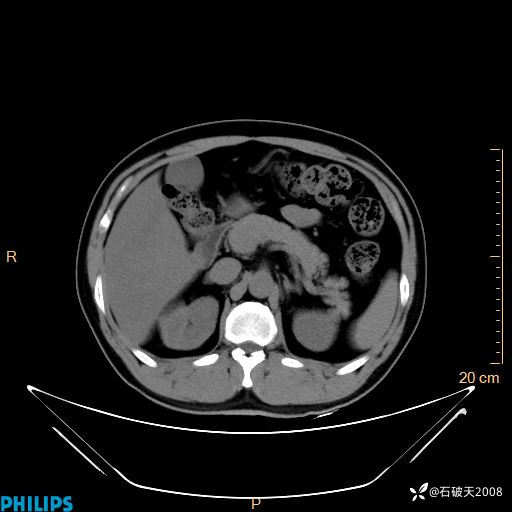

平扫轴位